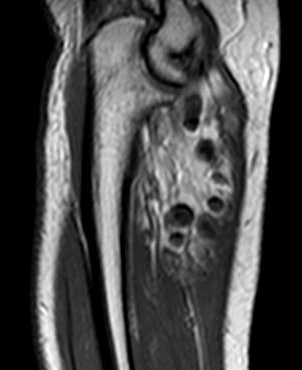

瘤软骨

瘤软骨为肿瘤细胞产生的软骨基质,多来源于软骨类肿瘤,或内有化生瘤软骨成分的其他肿瘤如成软骨型骨肉瘤。瘤软骨为软组织密度,未钙化时,主要通过 MRI 检查显示。由于瘤软骨多由富含水分及粘多糖的透明软骨构成,故 T1WI 呈偏低信号,T2WI 或 PDWI 呈明显高信号,被低信号的纤维间隔分开呈分叶状(图 24、图 25a-b),增强扫描多呈不均匀分隔状强化(图 25c),主要是纤维间隔强化,瘤软骨强化不明显之故。

图 24.瘤软骨:内生软骨瘤

图 25.瘤软骨:内生软骨瘤